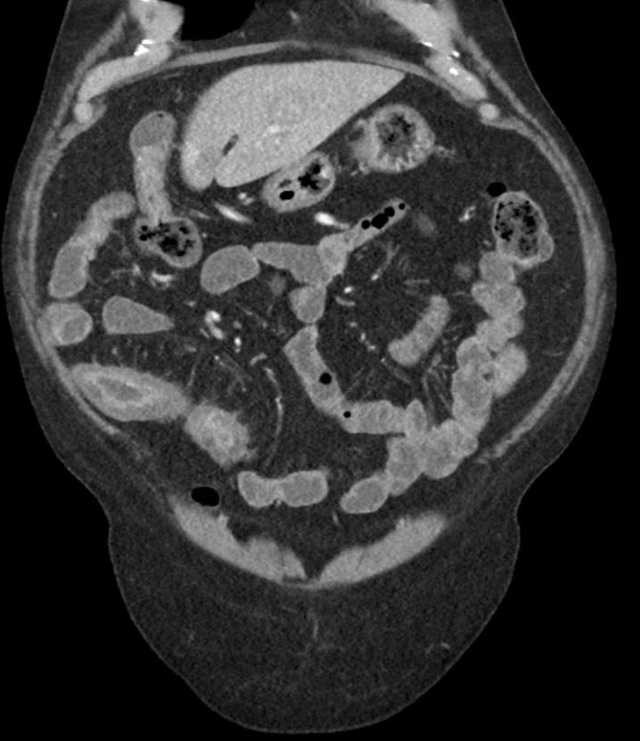

克罗恩病是一种慢性炎症性肠道疾病,会给日常饮食带来很多限制和挑战。我深刻体会到了饮食对疾病的影响,学会了慢慢调整自己的饮食习惯,寻找适合自己的饮食之道。